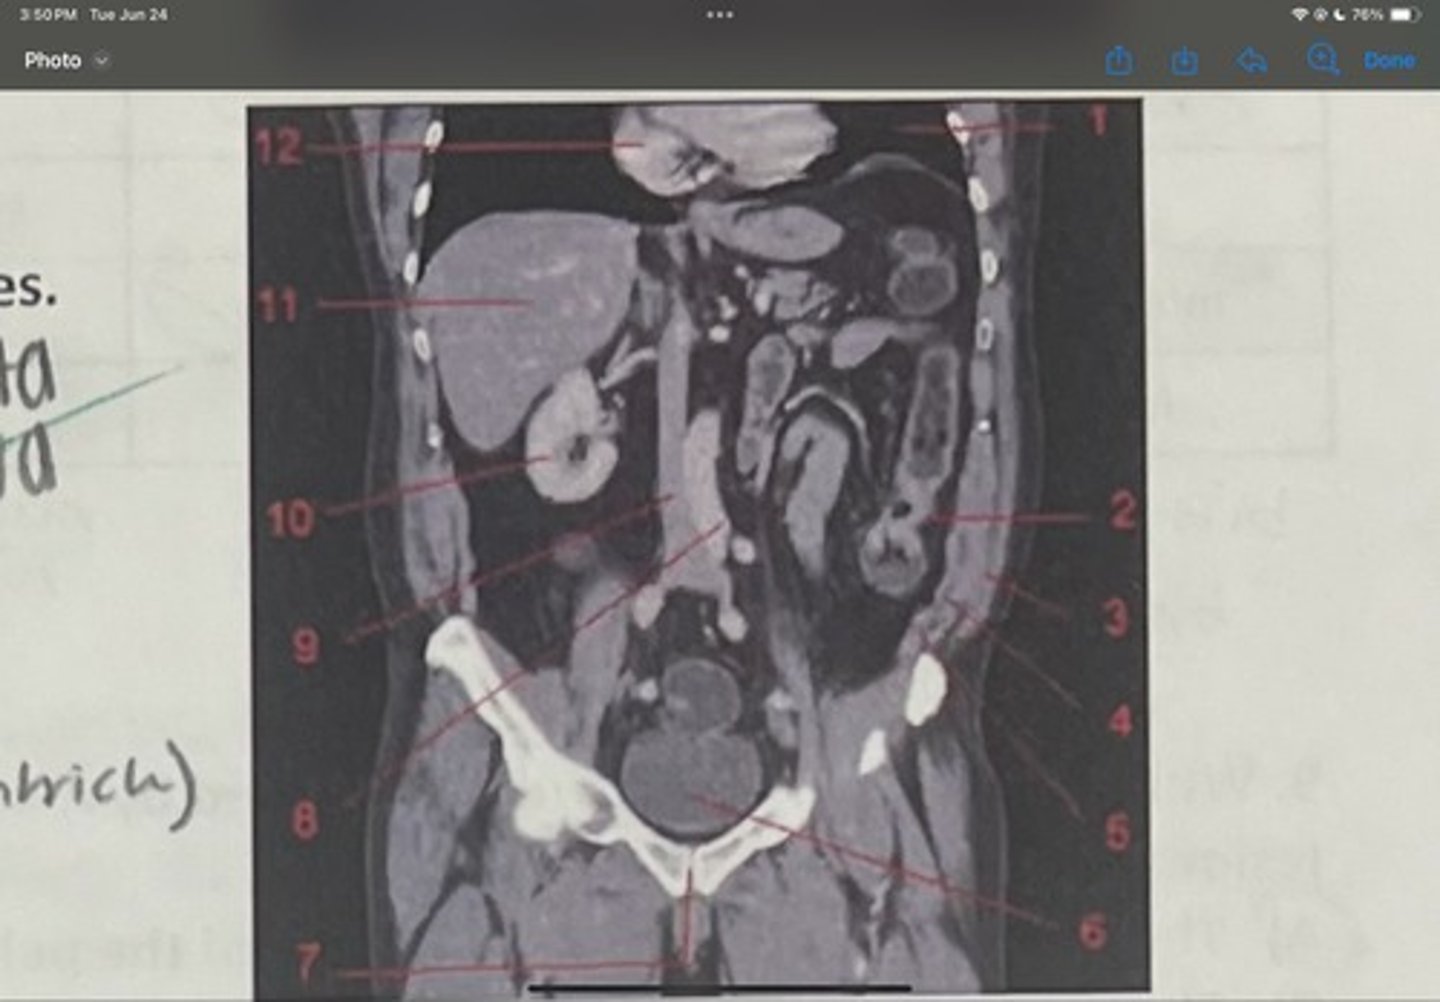

What is 1

Descending colon

What is 2

External oblique

What is 3

Internal obliques

What is 4

Transversus abdominis

What is 5

Bladder

What is 6

Pubic sysmphysis

What is 7

Abdominal aorta

What is 8

Inferior vena cava

What is 9

Right kidney

What is 10

Liver

What is 11

Heart (right ventricle)

What is 12

Subcostal nerve (T12)